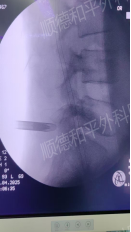

收住骨科二区(脊柱外科)后,张哉炯主任带领骨干医生,立即对其展开全面细致的检查。体格检查发现,患者腰椎生理曲度变直,活动轻度受限,左侧股神经牵拉试验阳性,左小腿后外侧皮肤感觉麻木,拇趾背伸肌力也减弱了。进一步的影像学检查更是“揪出”了隐藏的“罪魁祸首”:腰4/5、腰5/1、腰3/4椎间盘均存在变性、膨出及突出问题,不仅压迫神经根,还导致椎管继发性狭窄,同时伴有腰椎退行性变、终板炎、棘间韧带炎等一系列问题。

面对如此复杂的病情,结合患者保守治疗无效的过往,张哉炯主任带领的骨二区骨干医生团队严谨评估后,一致认为手术指征明显。在充分排除手术禁忌后,决定为其实施腰椎4/5椎间孔镜椎间盘摘除术,精准锁定关键责任椎体,直击病痛根源。